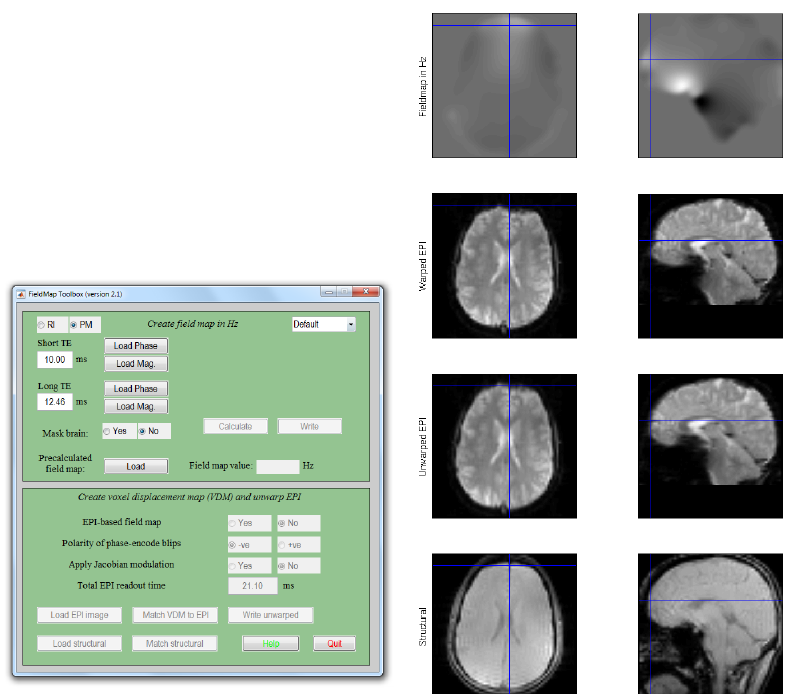

24 FieldMap Toolbox 173

24.1 Introduction ........................................173

24.7 Creating Field Maps Using the FieldMap GUI .....................178

24.7.1 Create field map in Hz ..............................178

24.7.2 Create voxel displacement map (VDM) and unwarp EPI ...........181